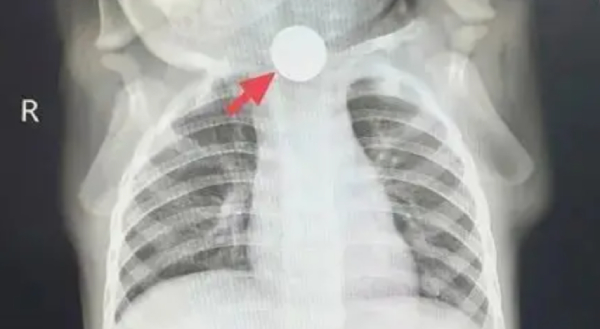

ผลเอกซเรย์ทำเอาทุกคนในห้องตรวจช็อก! ภาพฉายให้เห็นวัตถุทรงกลมติดค้างอยู่ที่หลอดอาหารส่วนบน... มันคือ "เหรียญ"

ความจริงกระจ่างทันที ที่น้องไม่กินข้าวเพราะเจ็บคอจนกลืนไม่ได้ ที่น้ำลายไหลเพราะเหรียญอุดทางเดินอาหารทำให้น้ำลายไหลย้อนกลับ และที่ไอเพราะน้ำลายไหลลงไปสำลักในหลอดลม ไม่ใช่เพราะเครียดหรือเป็นหวัดแต่อย่างใด